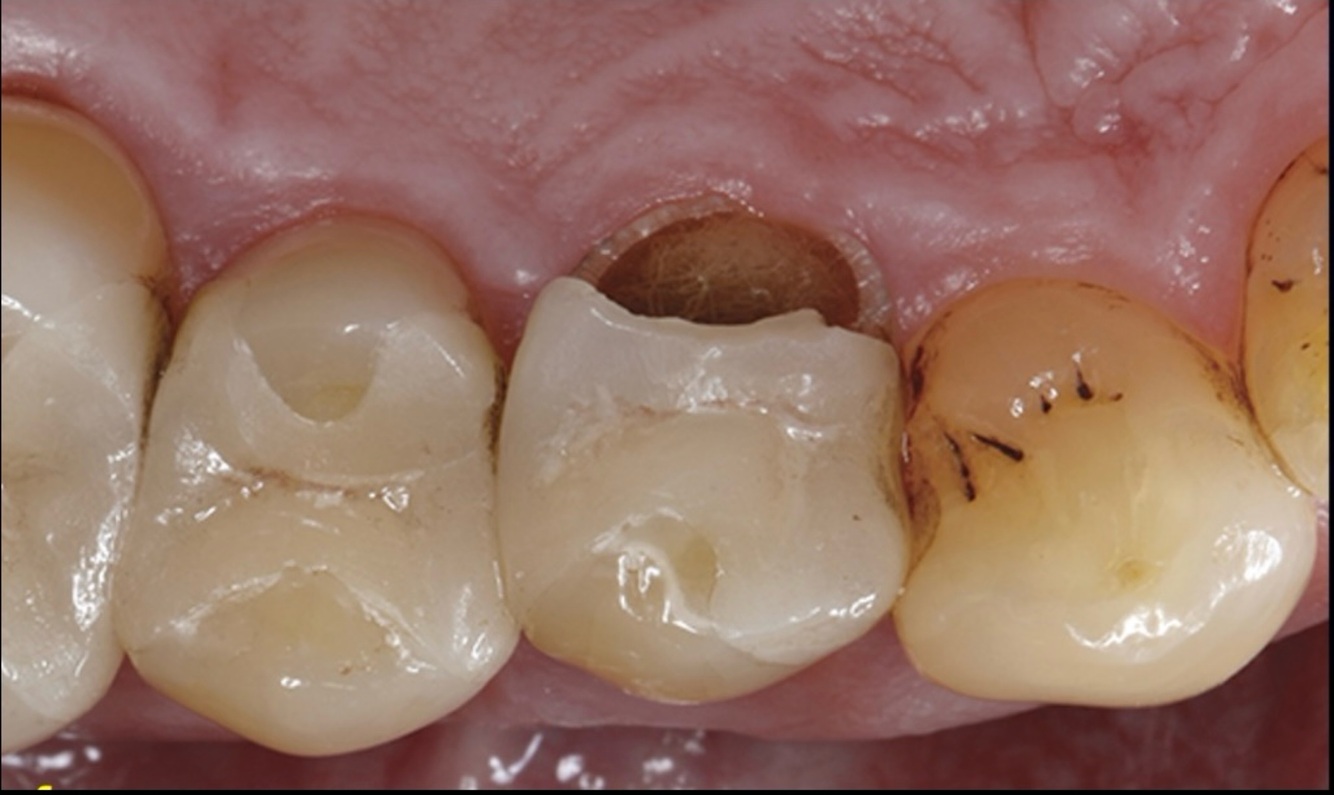

Q

The fractured restoration is on:

13

24

16

34

A